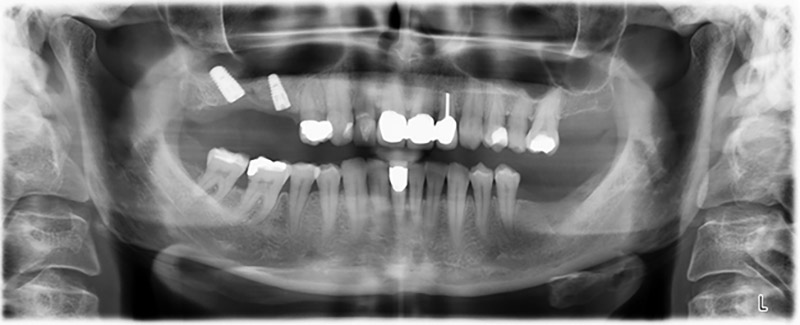

Para limitar el aumento a la región 14, se mantuvieron conversaciones con la paciente y se acordó una incorporación oblicua del implante 16 hacia la zona dorso-craneal (figura 8).

Este método permite exclusivamente una solución atornillada en la prótesis definitiva. Para que el puente pueda atornillarse en la zona oclusal, se necesita un pilar angulado (por ejemplo, a 35°) que permita el atornillado perpendicular a la zona de oclusión.